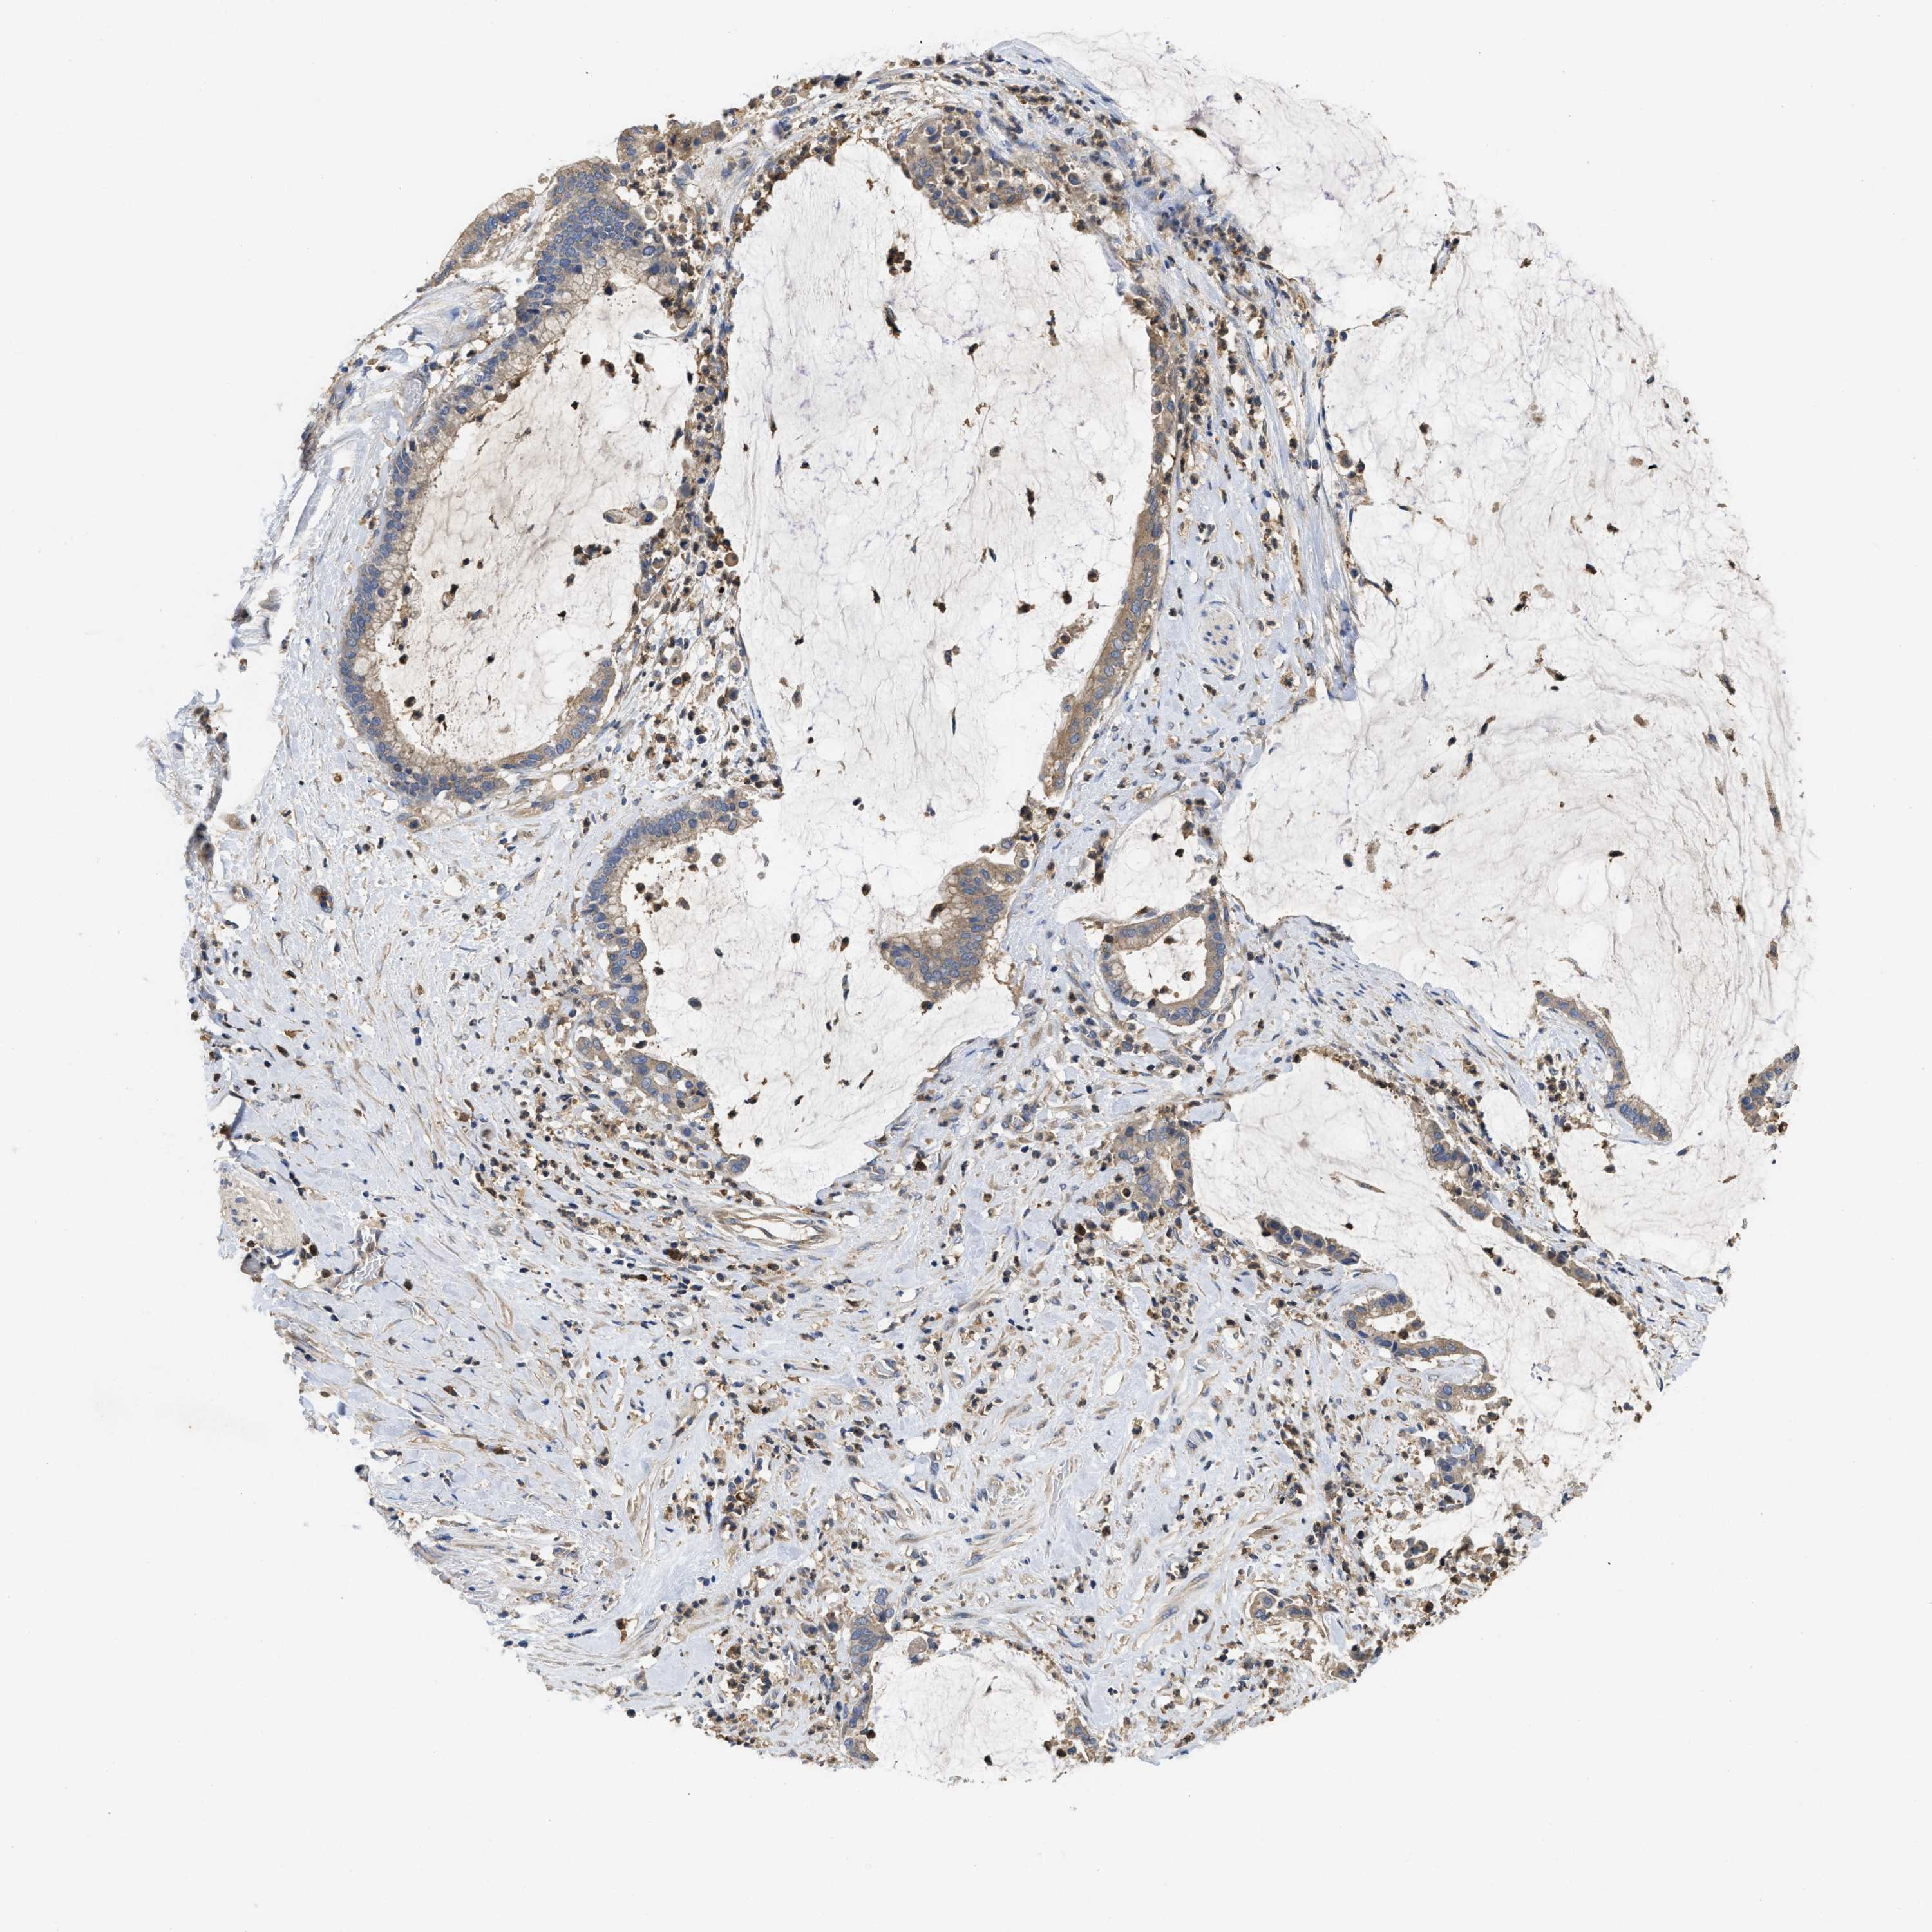

PANCREATIC CANCER - Protein expressioni

A mouse-over function shows sample information and annotation data. Click on an image to view it in a full screen mode. Samples can be filtered based on level of antibody staining by selecting one or several of the following categories: high, medium, low and not detected. The assay and annotation is described here.

Note that samples used for immunohistochemistry by the Human Protein Atlas do not correspond to samples in the TCGA dataset.

Antibody stainingi

Antibody staining in the annotated cell types in the current human tissue is reported as not detected, low, medium, or high, based on conventional immunohistochemistry profiling in selected tissues. This score is based on the combination of the staining intensity and fraction of stained cells.

Each image is clickable and will lead to virtual microscopy that enables deeper exploration of all samples and also displays staining intensity scores, fraction scores and subcellular localization as well as patient and tissue information for each sample.

Antibody HPA018955

Antibody HPA021123

Staining

High

Medium

Low

Not detected

Intensity

Strong

Moderate

Weak

Negative

Quantity

>75%

75%-25%

<25%

None

Location

Nuclear

Cytoplasmic/membranous

Cytoplasmic/membranous,nuclear

Adenocarcinoma, NOS